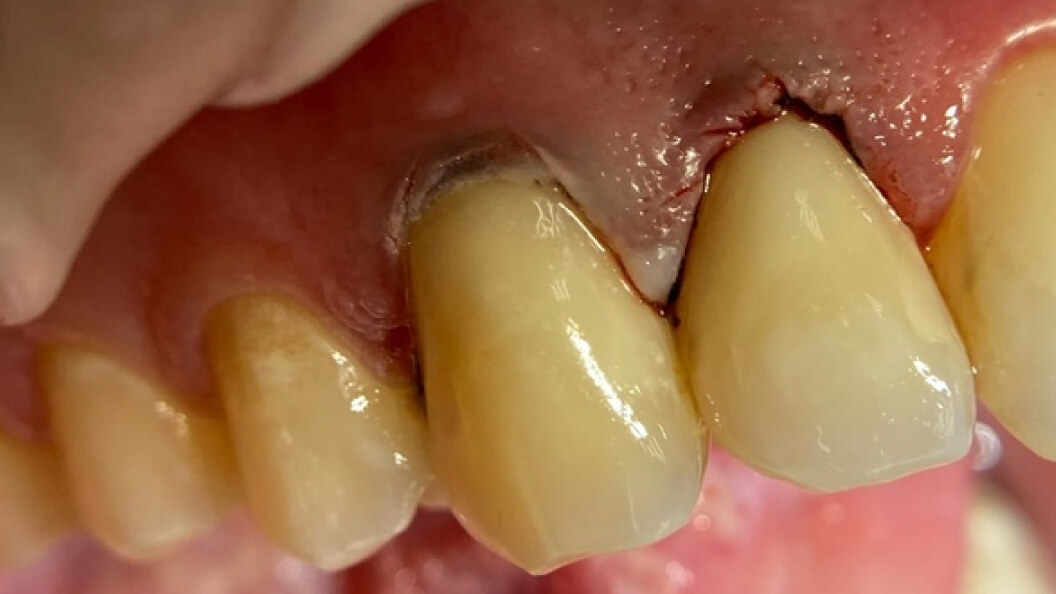

Пациентка обратилась в «Стоматологию Комфорта» с жалобами на эстетический дефект передних зубов. Врач Галухина Карина Николаевна во время осмотра выявила кариозные полости на 1.2. и 1.3 зубах. Было решено провести лечение с помощью пломбировочного материала Vitremer A3. Врач также рекомендовала рациональную гигиену полости рта после лечения.

В ходе лечения проведены следующие работы:

- введение анестетика;

- применение системы изоляции рабочего поля;

- наложение лечебной прокладки;

- наложение изолирующей прокладки;

- пломбирование композитом Vitremer;

- шлифовка и полировка пломбы;

- обработка полости рта.